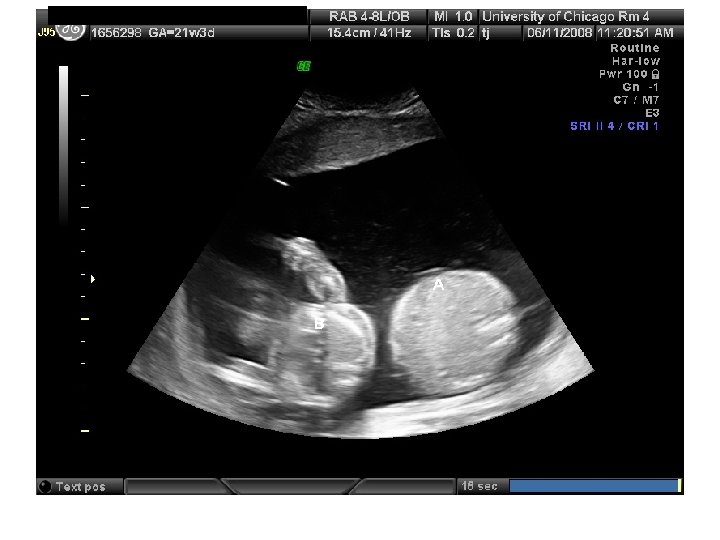

QUIZ What is Your Diagnosis? Case: Patient J. F. 30 years old, at 32 week gestation. Presented with the following pictures.

Answer: a) Trisomy 21 b) Non-immune Hydops c) Paravo virus Infection